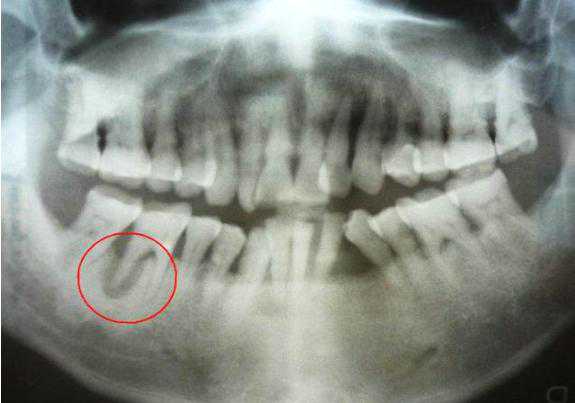

种植体代替人类的牙根,植入到人类的颌骨中。人类的第一副牙齿是乳牙,一共20颗。第二副牙齿是恒牙,一共28-32颗;种植牙也被称为人类的第三副牙齿。